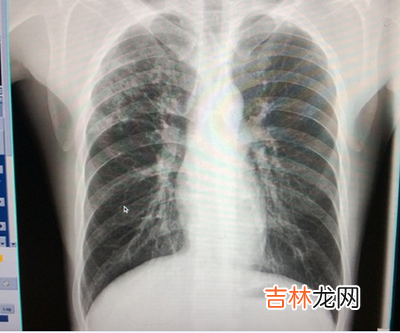

【上周北京市两人死于肺结核感染】

昨天,市卫生局发布最新疫情,上周本市各医疗机构共接报传染病患者4121例,其中有两名肺结核感染者死亡 。

文章插图